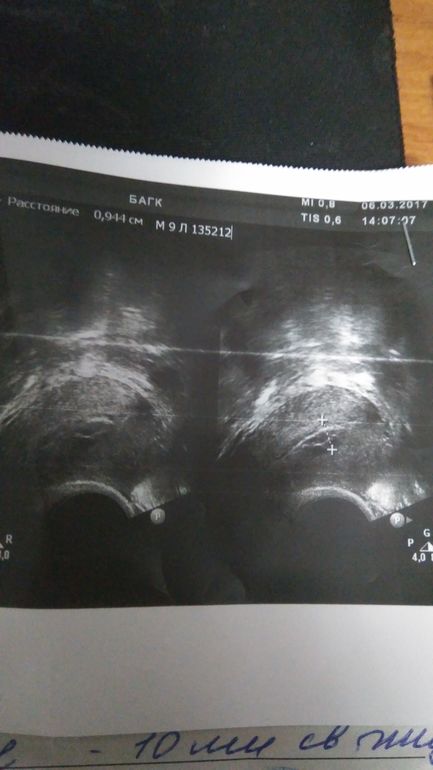

Девочки привет.Голова идет кругом... Планируем малыша 1,5 года, безуспешно.Ходила в этом месяце на очередную фолликулометрию.

О была на 14 дц,но жт не увидела узист,сказала,что доминантного фоллика нет,а жидкость есть.Предположила,что вот вот была О.Сегодня пошла,чтоб удостовериться что есть жт.Оно есть,но узист меня озадачила, сказав,что эндик неоднородный.Сказала,что может эндометрит.Но сейчас ставлю свечи Клеон-Д,лечу БВ.Разве может быть воспаление?Еще она сказала, что может такая реакция на Дюфастон.Мне в этом цикле назначили его.Вообще что это может быть?! Раньше такого не было(((